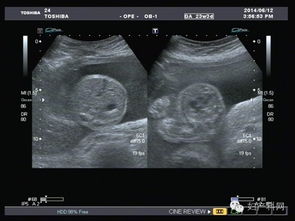

超聲波檢查,通過(guò)超聲波檢查出胎寶寶的體重、位置、大小。胎盤(pán)位置、羊水?dāng)?shù)量、呼吸運(yùn)動(dòng)等情況,以便判斷是進(jìn)行自然分娩還是剖腹產(chǎn)

特別是對(duì)于月經(jīng)不準(zhǔn)或者記不清楚最后一次月經(jīng)的孕媽媽來(lái)說(shuō),在懷孕早期可以利用超聲波檢查預(yù)見(jiàn)預(yù)產(chǎn)期。還可以檢查胎兒是否缺氧,或者孕婦是否是宮外孕。但是,超聲波最主要的還是堅(jiān)持寶寶在腹中的生長(zhǎng)情況。

現(xiàn)代社會(huì),雖然科技在不斷發(fā)展,但是環(huán)境也在受到更嚴(yán)重的污染,這就導(dǎo)致了許多畸形胎兒的生長(zhǎng),而超聲波檢查就能告訴你胎兒生長(zhǎng)是不是正常,是否有什么缺陷,有特別的情況的話,醫(yī)生通過(guò)超聲波檢查可以告訴你,比如,有些遺傳病可以在寶寶出生之前檢查出來(lái),比如營(yíng)養(yǎng)性肌肉發(fā)育不良,如果是男孩的話很容易造成遺傳,這樣的話醫(yī)生會(huì)通過(guò)檢查結(jié)果告訴你最好不要孩子。

一般來(lái)說(shuō),在第18周-20周進(jìn)行第一次超聲波檢查。它能大致診斷出胎兒是否畸形,觀察胎兒的活動(dòng)狀態(tài)。